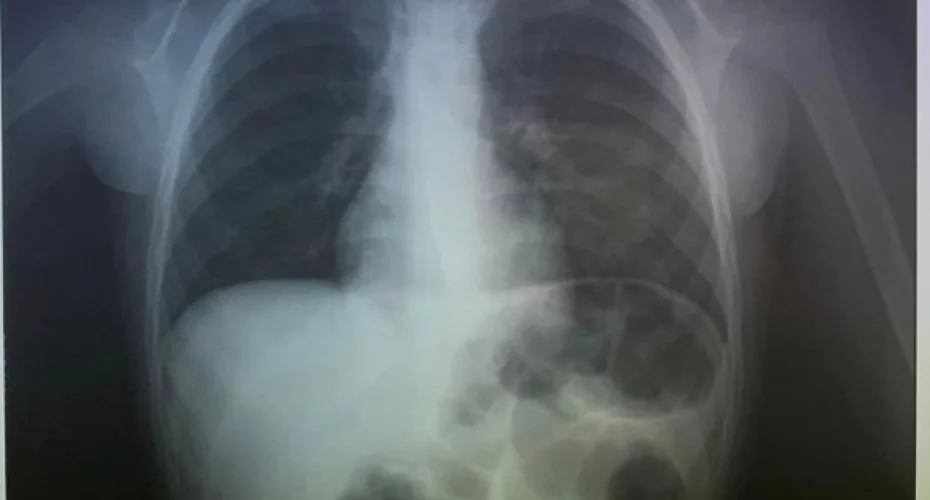

Докторите прво направиле рендген, за да видат каде заврши паричката и виделе дека е заглавена во грлото.

Лекарите по интервенцијата објавиле фотографии на Фејсбук.

„Се простивме од 2023 година со итно вадење на паричка проголтана од момче (4). Среќна Нова Година“, напишаа тие.